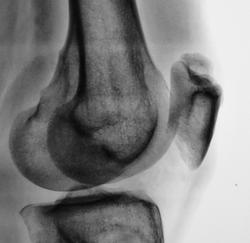

Травма. Направлен на рентгенографию коленного сустава

И мне это не понравилось. И по боковой - впечатление о смещении фрагмента.

Мужчина 39 лет, жалоб нет. Обратил внимание на разницу с другим коленным суставом (выпирает). Второй сустав на снимке без изменений. Травм утверждает, что не было.

Получается просто удвоение наколенника ....не попадалось